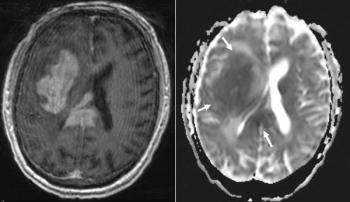

A 74-year-old man with a medical history of hypertension, hyperlipidemia, and type 2 diabetes mellitus was found lying on the ground by his family and was brought to the emergency department, where he was found to have left facial drooping and weakness. What is the most likely diagnosis?